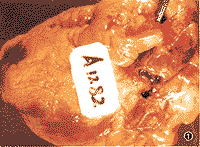

第47例:猝死

病历摘要

患者男性,77岁,于1997年10月22日晨被家人发现屈曲倒地,呼之不应,8时15分医生赶到查患者已无呼吸、脉搏,双瞳孔直径约1mm,无对光反射,抢救无效。既往史:1965年诊断高血压,血压最高为190/110mmHg(1 mmHg=0.133 kPa),1981年后坚持服药,血压在135~180/70~100 mmHg之间。1977年因“早搏”、心电图(ECG)示窦性心动过缓、冠状动脉供血不足,诊为冠心病,无明确心绞痛病史。1979年起血脂增高,未服用降脂药物。1991和1994年两次因脑供血不足住院治疗。1979年胃镜检查,诊断萎缩性胃炎伴肠上皮化生。1982和1992年分别发现左眼和右眼闭角型青光眼,一直用匹罗卡品滴眼治疗。此外还有慢性支气管炎、肺气肿、肝炎及十二指肠溃疡史。吸烟40余年,40支/天,1981年戒烟。有时饮酒,量少。

辅助检查:(1)1980~1997年多次检查肝肾功能、血糖,基本正常,尿蛋白偶见微量;(2)1979~1997年血胆固醇为5.2~7.9 mmol/L,甘油三酯1.13~3.06 mmol/L,高密度脂蛋白胆固醇1.04~1.69mmol/L;(3)1997年X线胸片:双肺气肿,双下肺纹理粗,右肋膈角模糊,主动脉迂曲,主动脉弓钙化,心脏外形不大;(4)1997年ECG示窦性心动过缓 ......